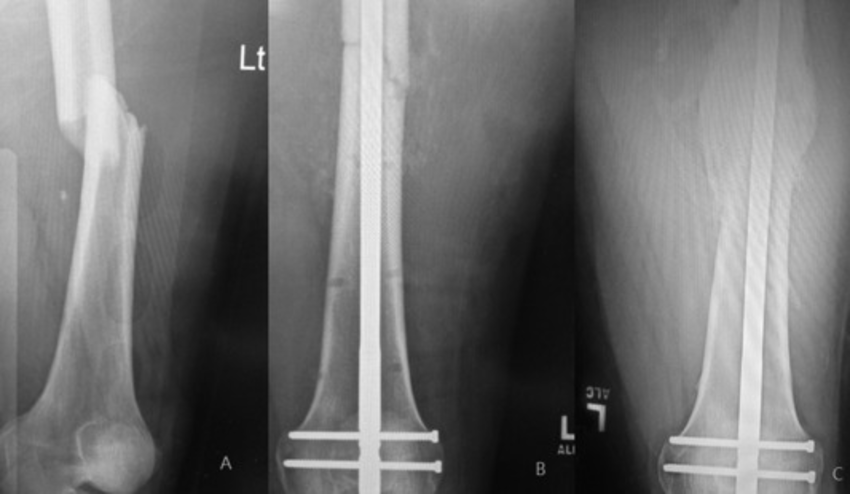

Intramedullary Nailing involves inserting a metal rod, or nail, into the central cavity of a long bone (the medullary canal). The nail is designed to keep fractured bone segments aligned and stable during healing. Once placed within the bone, the nail is secured with locking screws at each end to hold the fragments in place.

1. Anaesthesia: Performed under general or regional anaesthesia to keep the patient comfortable.

2. Incision and Access: A small incision is made near one end of the fractured bone to access the medullary canal.

3. Insertion of the Nail: The surgeon carefully inserts the nail into the canal, positioning it to span the fracture site.

4. Locking Screws Placement: Screws are placed through the bone and nail at each end to securely lock the nail in place, maintaining alignment and stability.

5. Wound Closure: Incisions are closed, and a dressing is applied.